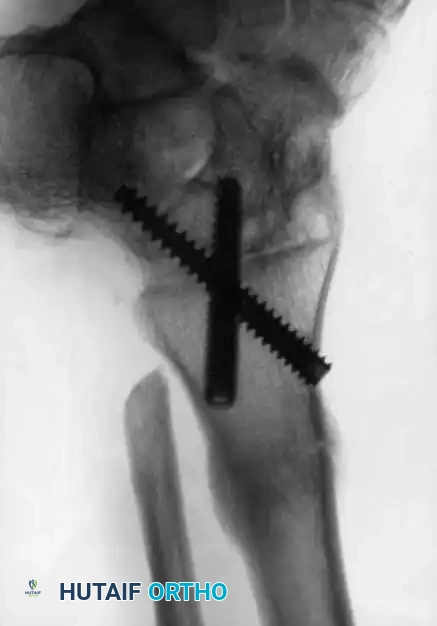

Image

Advanced hemophilic arthropathy of the ankle often requires aggressive intervention. When arthroscopic synovectomy fails to control symptoms in end-stage disease, definitive stabilization via ankle arthrodesis utilizing rigid internal fixation becomes necessary to eliminate pain and prevent further hemorrhagic episodes.